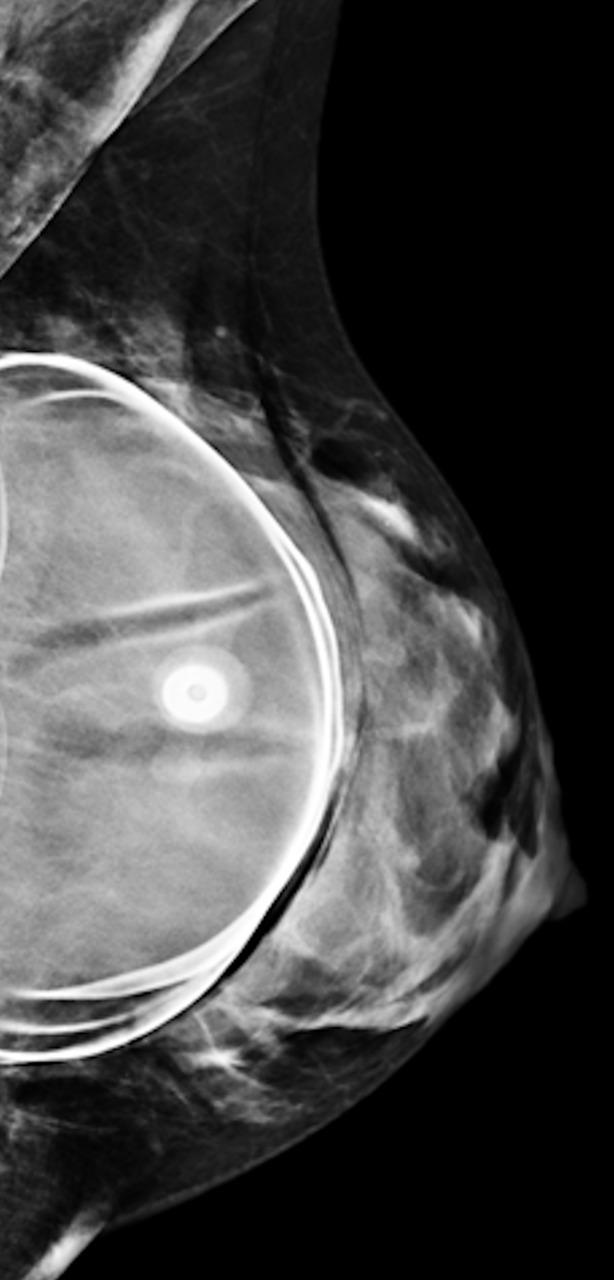

En mammographie : aspect rond, régulier, hyperdense si en silicone (fig. 1), moins dense en cas de sérum physiologique (fig. 2). Confirmé par la tomosynthèse (3D), à utiliser avec parcimonie en raison de l’exposition aux rayons.

• extracapsulaire (fig. 3 et 4), contenu hétérogène avec échos internes et perte du contour régulier de la paroi à l’échographie. Diagnostic confirmé par l’IRM mammaire avec séquences dédiées silicone, qui montre l’incontinence de la prothèse (paroi irrégulière) et des dépôts de silicone rétro- ou périprothétiques. Des ganglions chargés en silicone peuvent être visibles.